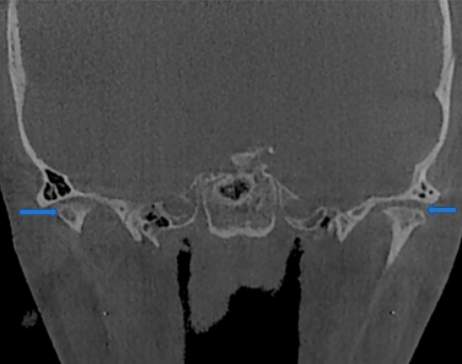

Para realizar un diagnóstico preciso, es crucial utilizar pruebas de imagen, como radiografías panorámicas, que permiten descartar patologías dentales como causa de dolor referido, así como identificar anormalidades en los cóndilos de la rama mandibular que puedan indicar un proceso degenerativo incipiente. Otra prueba de gran utilidad es la tomografía computarizada de haz cónico, que proporciona imágenes detalladas de las estructuras óseas de la articulación, como quistes subcondrales, erosiones, esclerosis generalizada u osteofitos. Sin embargo, esta técnica no permite visualizar el disco articular en su totalidad. Para obtener una evaluación completa de la posición y morfología del disco, así como para detectar cambios óseos degenerativos y derrames articulares, se recomienda el uso de resonancia magnética.